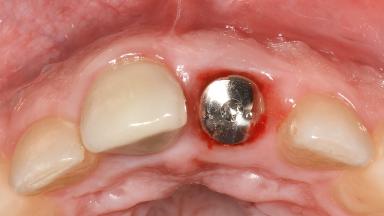

Peri-Implant Mucositis Associated with Misfit of a Cemented Restoration

A 37-year-old male patient was referred to the Department of Periodontology at the University of Bern, Switzerland, by a private dentist. Tooth 21 had been lost due to trauma and had been replaced with an implant and a cemented single crown. The tapered-effect tissue-level implant had a diameter of 4.1 mm, a length of 12 mm, and a sandblasted and acid-etched (SLA) surface (Straumann Dental lmplant System; Institut Straumann AG, Basel, Switzerland). The metal-ceramic crown had been cemented permanently, leaving a submucosal gap between the implant shoulder and the crown margin. Absence of marginal bone loss apical to the polished transmucosal neck of the implant could be observed .